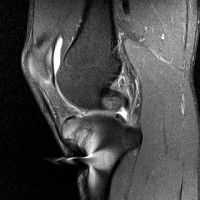

무릎 mri 간단히 봐주실 수 있으시나요 ㅠㅠ

안녕하세요 8년전 십자인대 수술하고 최근 무리한 운동에 무릎 불편감이 생겨서

mri 찍었습니다.

진단결과는 첫 찍은 병원에서 활액막염 이라는 진단을 받았습니다. 혹시 봐주실 수 있으실까요?

진단결과가 달라 혼란스럽습니다 ㅠㅠ

• 안녕하세요. 강성주 의사입니다.

올라온 MRI가 단편적이라서 정확한 진단에 어려움이 있지만 십자인대에는 큰 이상이 있지는 않은것 같으며, 무릎관절내 물이 있는 것으로 보아 활액막염의 진단이 맞을 것 같습니다.

하지만 단편적인 영상이기 때문에 촬영병원에서 정확한 판독지 등을 받으시는 것이 좋겠습니다.